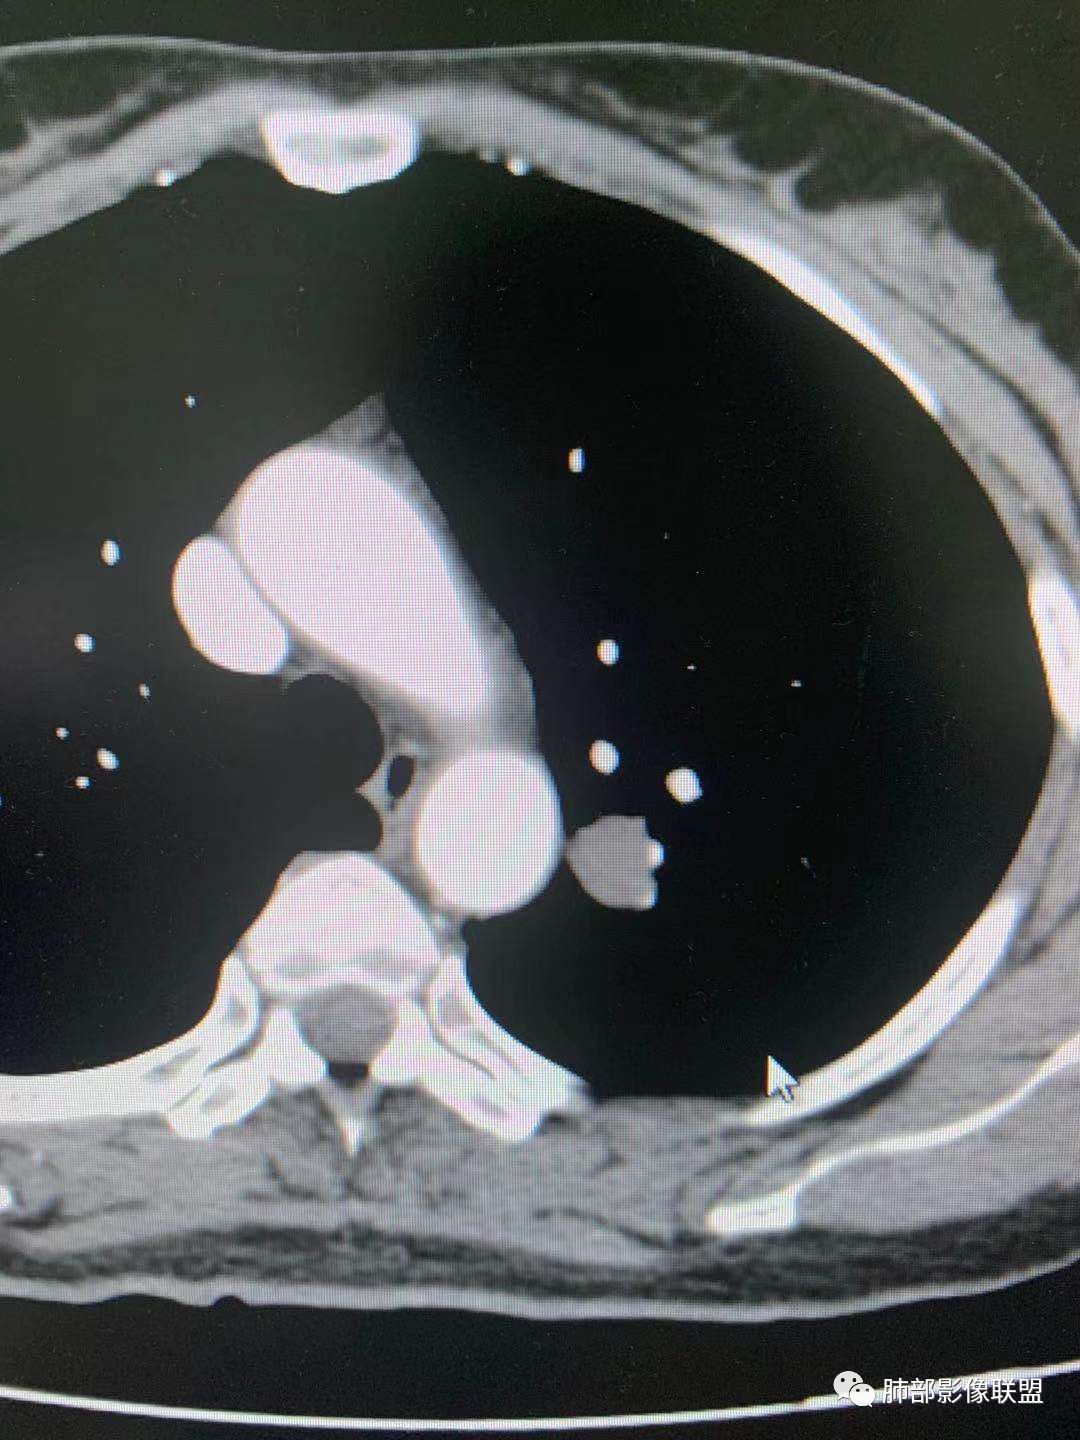

左肺上叶实性结节,边缘光滑清晰,血管贴边,渐进性延迟强化,密度均匀,考虑PSP.

贴边血管征,强化延迟,考虑PSP

左肺上叶实性结节,边缘光滑清晰,血管贴边,渐进性延迟强化,密度均匀,考虑PSP.但是强化幅度不够,需要鉴别早期肺癌 医学百科网 | YxBaike.Com

最大的靠后,有血管贴边征,渐进性明显强化,考虑PSP可能大

首先考虑PSP,周围可疑磨玻璃,鉴别恶性病变 医学百科网 | YxBaike.Com

中年女性,左肺上叶实性圆形结节,边缘有晕,血管及支气管贴边,强化尚均匀,渐进性明显强化,考虑为PSP可能